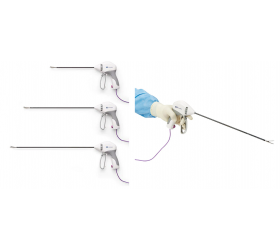

Ampla oferta de cateteres para tratamento de acesso arterial, venoso e AV em vasos variando de 1,5 mm a grandes vasos iliofemorais

Especificações de Cateter

| Modelo | Indicação | Plataforma de Liberação | Diâmetro Mínimo do Vaso | Comprimento do Cateter | Diâmetro do Cateter | Fio-guia | Power Pulse™ Habilitado | Fio-Guia Alternável | Porta de Injeção de Contraste |

|---|---|---|---|---|---|---|---|---|---|

| ZelanteDVT™ | Venoso | OTW | 6 mm | 105 cm | 8 F | 0,035” | Sim | Sim | Sim |

| Solent™ Omni | Acesso AV, Arterial e Venoso Periférico | OTW | 3 mm | 120 cm | 6 F | 0,035” | Sim | Sim | Sim |

| Solent™ Proxi | Acesso AV, Arterial e Venoso Periférico | OTW | 3 mm | 90 cm | 6 F | 0,035” | Sim | Sim | Sim |

| Solent™ Dista | Arterial Periférico | OTW | 1,5 mm | 145 cm | 4 F / 3 F | 0,014” | Sim | N/A | N/A |

| AVX™ | Fístula e Enxertos de Acesso AV | OTW | 3 mm | 50 cm | 6 F | 0,035” | N/A | N/A | Sim |